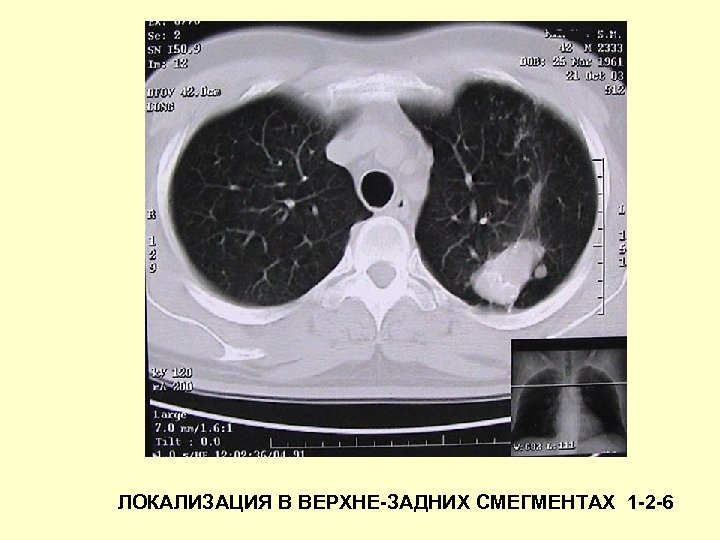

ЛОКАЛИЗАЦИЯ В ВЕРХНЕ-ЗАДНИХ СМЕГМЕНТАХ 1 -2 -6

Туберкулёз лёгких у взрослых: рентгенология • 1 -2 -6, реже 10 -й сегменты • Наличие «очагов отсевов» • Высокая вероятность распада при полисегментарном поражении • Медленная динамика